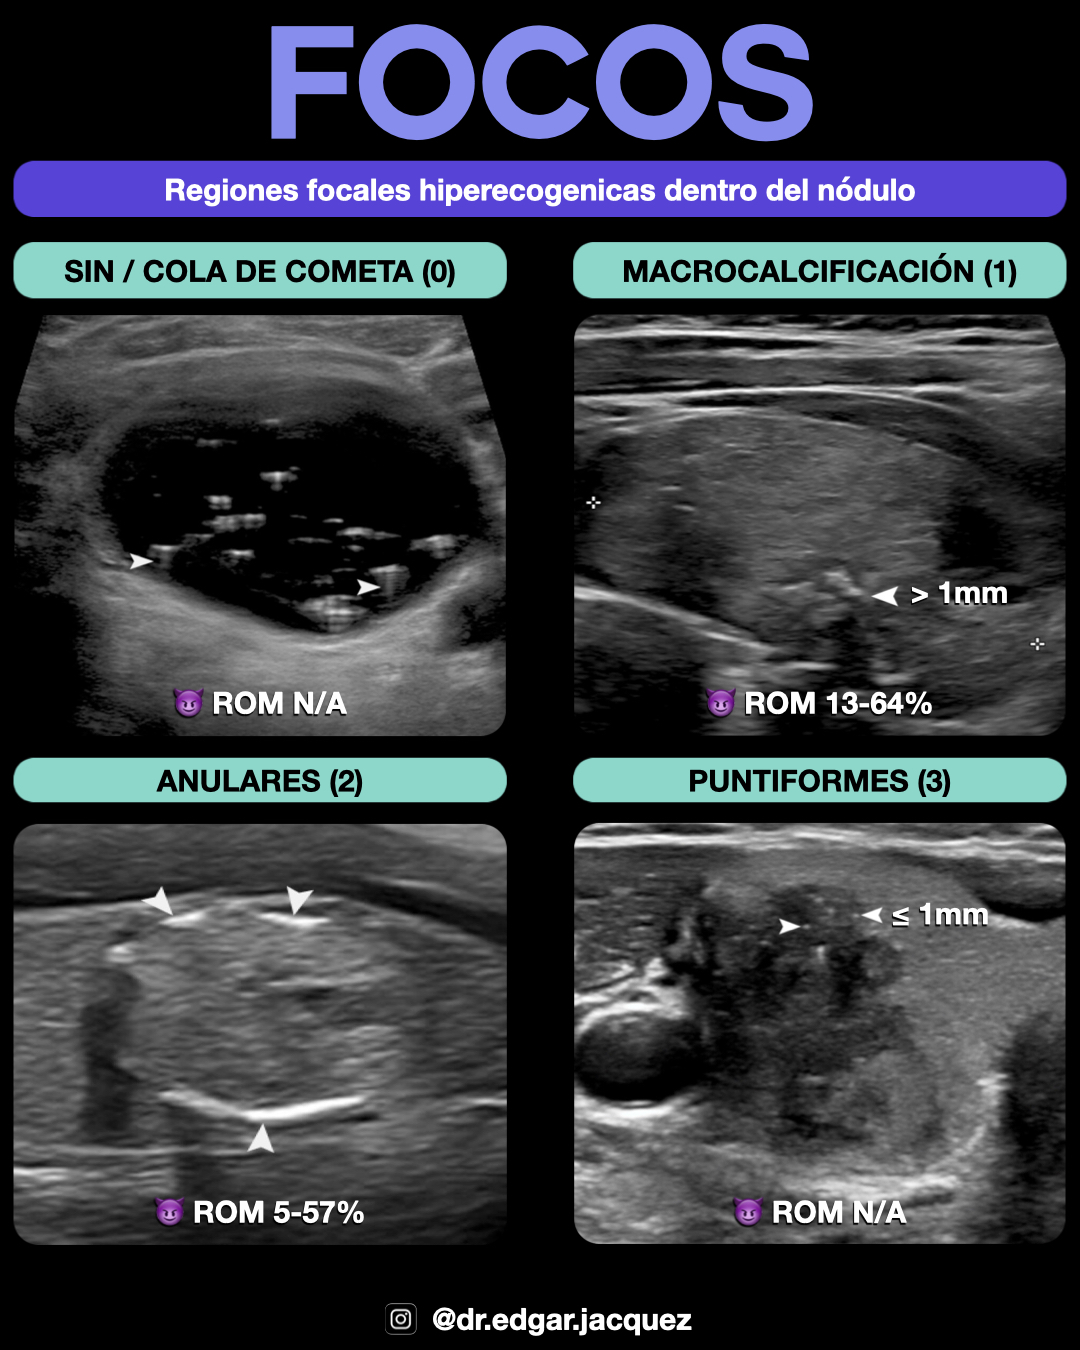

| Focos Ecogénicos | Ninguno (0), Macrocalcificaciones (1), Periféricas/Rim (2), Microcalcificaciones/Punteados (3) |

*Nota: Los puntos de focos ecogénicos son aditivos. *Cuando una característica no está clara, se le asignan 0 puntos.